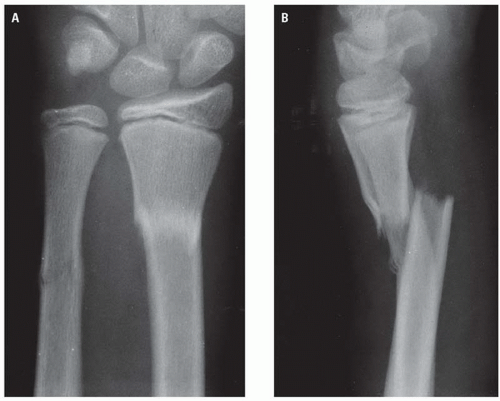

reverse colles fracture x ray

Reverse colles fracture x ray. Distal radius fractures are the most common orthopaedic injury. For a discussion of this fracture refer to the article on smith fractures. Complications may include damage to the median nerve. This describes the volar angulation of the distal fragment of an extra articular fracture of the distal radius the reverse of a colles fracture with or without volar displacement.

In fact the reverse barton fracture is a type ii smith fracture. This is caused when there is rupture in the end of radial bone located near wrist. A colles fracture is a type of fracture of the distal forearm in which the broken end of the radius is bent backwards. Smith fracture is also termed as reverse colles fracture.

The term is sometimes used to describe intra articular fractures with volar displacement. It is caused by a direct blow to the dorsal forearm or falling onto flexed wrists as opposed to a colles fracture which occurs as a result of falling onto wrists in extension. Dorsal angulation and shortening. Sometimes referred to as a reverse colles fracture this is an example of the most common type i smith fracture extra articular transverse fracture through the distal radius accounting for 80 90 of cases.